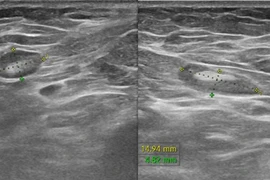

Kết quả chụp CT mạch máu não sau đó xác nhận bệnh nhân bị vỡ túi phình động mạch cảnh trong trái, đồng thời phát hiện thêm một túi phình động mạch cảnh trong phải chưa vỡ. Đây là tình trạng đặc biệt nguy hiểm, bởi túi phình động mạch não khi vỡ có thể làm tăng áp lực nội sọ, gây tổn thương não lan rộng, dẫn đến hôn mê sâu hoặc tử vong nếu không được can thiệp kịp thời.

Ngay lập tức, các bác sĩ Ngoại Thần kinh tiến hành phẫu thuật dẫn lưu não thất ra ngoài nhằm giảm áp lực nội sọ do xuất huyết. Sau đó, bệnh nhân được thực hiện chụp và can thiệp mạch số hóa xóa nền, tiến hành nút phình động mạch não.